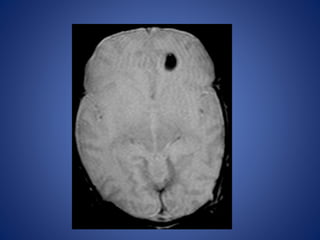

Vascular malformations

The common risk factors for children with hemorrhagic stroke :

• Arteriovenous malformations (AVMs)

• Aneurysms

• Cavernous malformations

14 yr male with headache and seizures.

Vascular malformations The commonrisk factors for children with hemorrhagic stroke : • Arteriovenous malformations (AVMs) • Aneurysms • Cavernous malformations

• 41.

14 yr malewith headache and seizures.